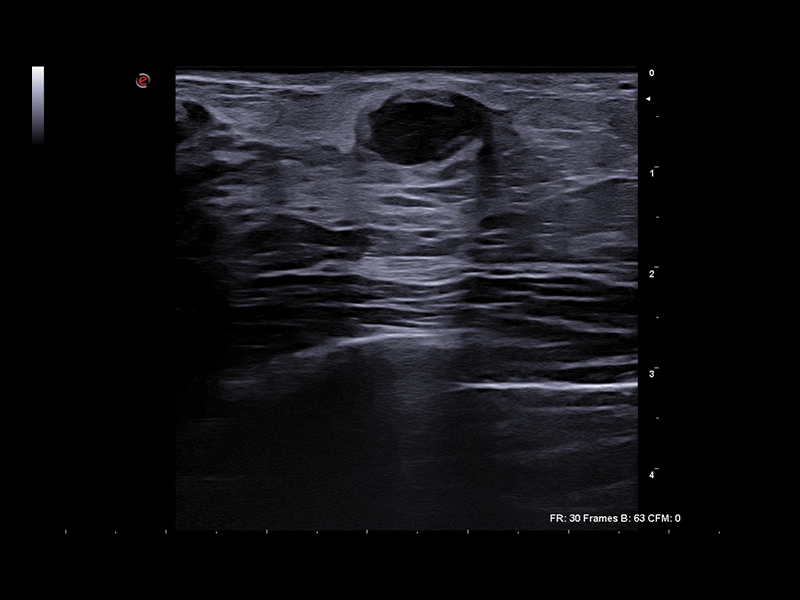

Clinical Images

Breast clinical image